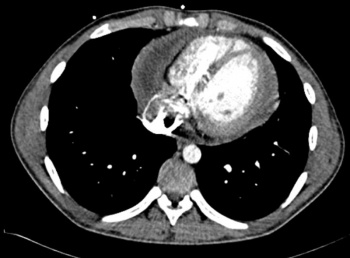

Figure 4: Subcostal view showing a thick exudative pericardial effusion. Thick fibrinous strands can be seen crossing the space and tethering the myocardium to the pericardium

Figure 4: Subcostal view showing a thick exudative pericardial effusion. Thick fibrinous strands can be seen crossing the space and tethering the myocardium to the pericardium(click to enlarge)

Surprisingly the echocardiogram showed a large pericardial effusion containing thick viscid heterogenous fibrin rich exudate with evidence of septation loculation, and organisation, indicating that these changes were not acute. There was Doppler evidence of pericardial constriction; however, the absence of bi-atrial enlargement suggested that it might be fairly recent.

LV and RV function were moderately impaired with EF of 30-40% due to a combination of adhesion and tethering and constriction, hence the compensatory tachycardia to maintain cardiac output.